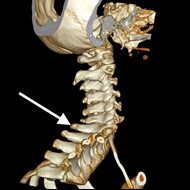

Na obrazie TK zaznaczono zatokę

Ilustracja do pytania 16

A. czołową w przekroju czołowym.

B. czołową w przekroju strzałkowym.

C. szczękową w przekroju strzałkowym.

D. szczękową w przekroju czołowym.